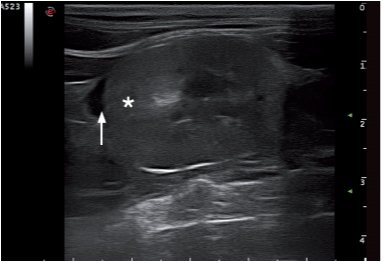

脂肪组织炎或肠系膜脂肪感染会呈现高回声。脂肪组织炎会出现在损伤的周围,例如胰腺炎,肠道损伤,手术伤口的周围(图13)。